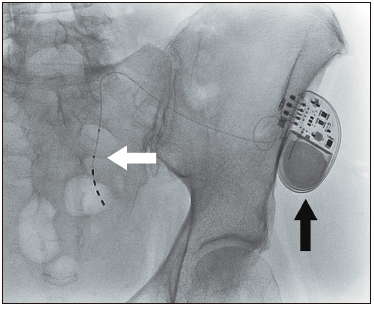

Las contraindicaciones relativas para el SNM incluyen la enfermedad neurológica

severa o rápidamente progresiva o la anatomía sacra anormal. La implantación consta de dos fases; la primera

de prueba, en la que se determina si el tratamiento aporta beneficios al paciente en particular, con la

colocación de un electrodo a nivel de la segunda vértebra sacra (S2), y la segunda de implante definitivo,

el cual se realiza solo en los pacientes que tuvieron éxito en la fase de prueba (Figura 2).

Se

considera una fase de prueba exitosa cuando, en un lapso de 2 a 3 semanas, los síntomas mejoran en más del

50%.

Figura 2. Radioscopía de fase de implementación de neuromodulador

sacro. Se observa el electro en forma de “jota” a nivel del foramen de S2 (flecha blanca) y el generador

subcutáneo ya implantado en el glúteo izquiedo (flecha negra). La implantación se realiza bajo sedación

anestésica y en forma ambulatoria